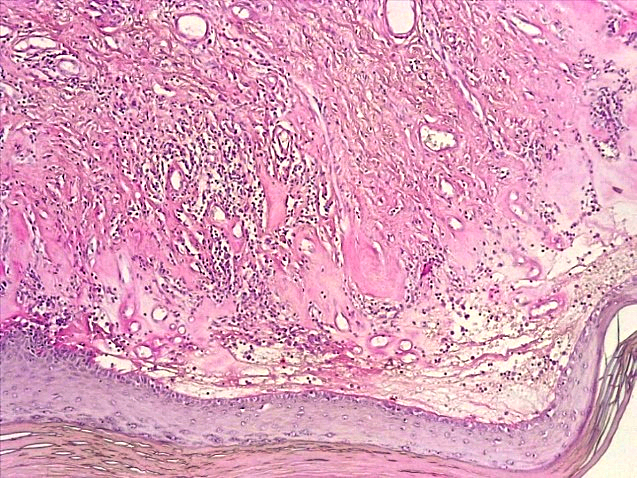

При морфологическом исследовании биоптатов вульвы пациенток с атрофическим вариантом течения СЛВ наибольшие изменения наблюдались со стороны эпидермиса и поверхностных слоев дермы. В эпидермисе отмечалась резкая атрофия клеток многослойного плоского эпителия (МПЭ) с участками повышенного ороговения (гиперкератоза и паракератоза), в некоторых случаях были выявлены участки фибриноидного некроза с окружающей лейкоцитарной клеточной инфильтрацией (рис. 1), указывающие на наличие очагов острого язвенного повреждения эпидермиса на фоне дистрофических и регрессивных изменений многослойного плоского эпителия. При этом количество клеточных слоев эпидермиса было уменьшено в среднем до 3–4 с избыточным образованием роговых чешуек в поверхностных слоях, а количество базальных клеток эпидермиса в 1 мкм не превышало 10, что свидетельствовало об атрофии резервного слоя эпидермиса (рис. 2).

Рис. 1. Атрофический вариант течения СЛ вульвы. Участок фибриноидного некроза с лейкоцитарной инфильтрацией многослойного плоского эпителия с развитием паракератоза, дискератоза. Развитие плотной волокнистой соединительной ткани в поверхностных слоях дермы с умеренной лимфо-гистиоцитарной инфильтрацией (окраска гематоксилином-эозином, х100)

Fig. 1. Atrophic variant of the course of the vulva SL. A site of fibrinoid necrosis with leukocyte infiltration of multilayer squamous epithelium with the development of parakeratosis, dyskeratosis Development of dense fibrous connective tissue in the superficial layers of the dermis with moderate